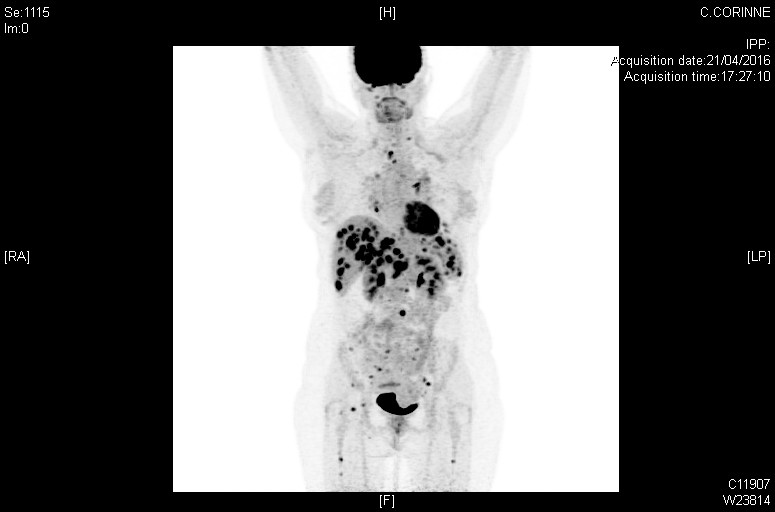

Scanner

Atteintes systémiques diffuses dans le cadre d'une sarcoïdose (TEP-scan)